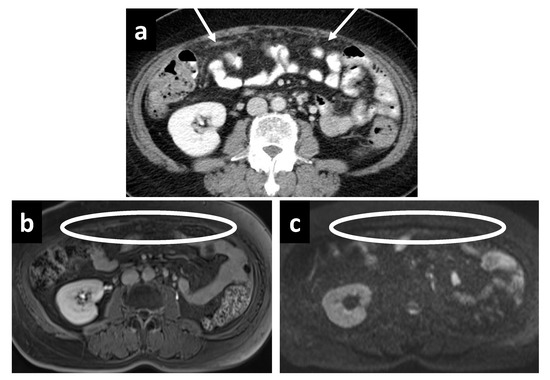

3.3. Evaluation of PCI